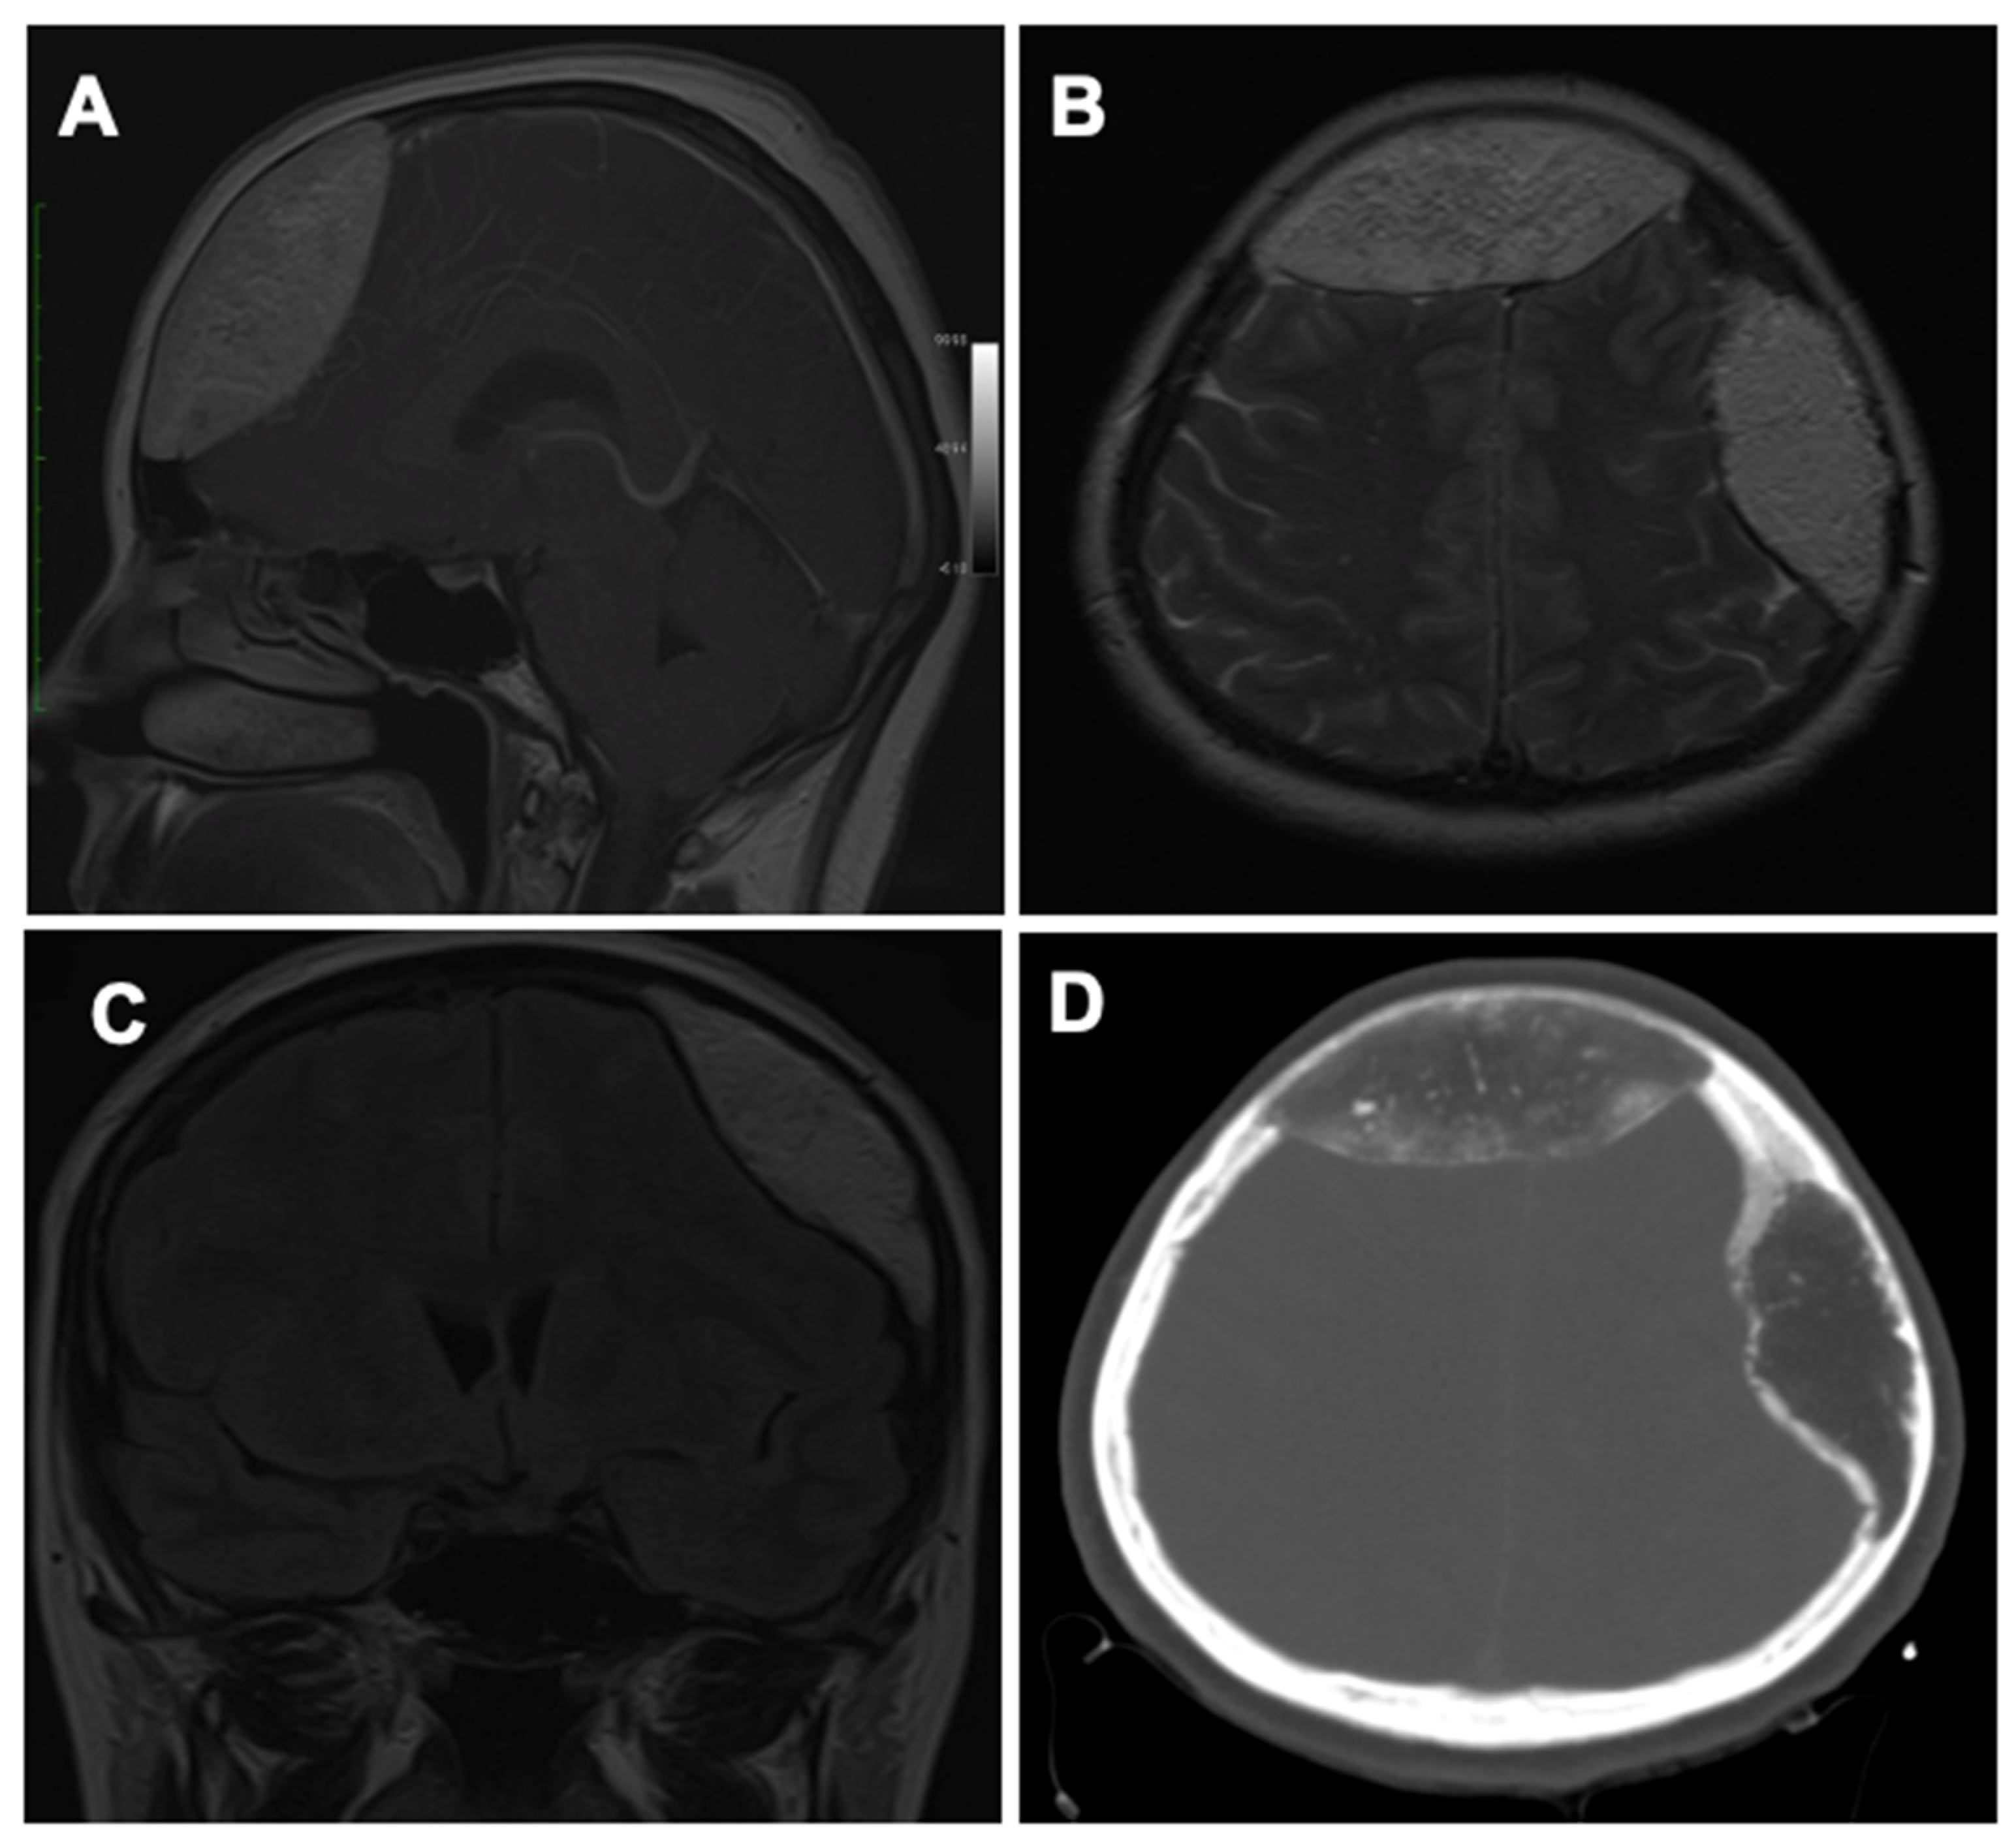

| Current study | 50/F | Frontal bone and left parietal bone | Frontal and parietal headache, nausea, and vomiting | Symptoms increasing in intensity from a month before | CT and MRI: two hypodense lesions (7 cm and 8 cm) with multiple interior calcifications and compressive effect on the cerebral parenchyma | En-bloc resection in two stages: 1. Frontal craniotomy and reconstruction with intact external plate; 2. Left parietal craniotomy with titanium and PMMA cranioplasty |